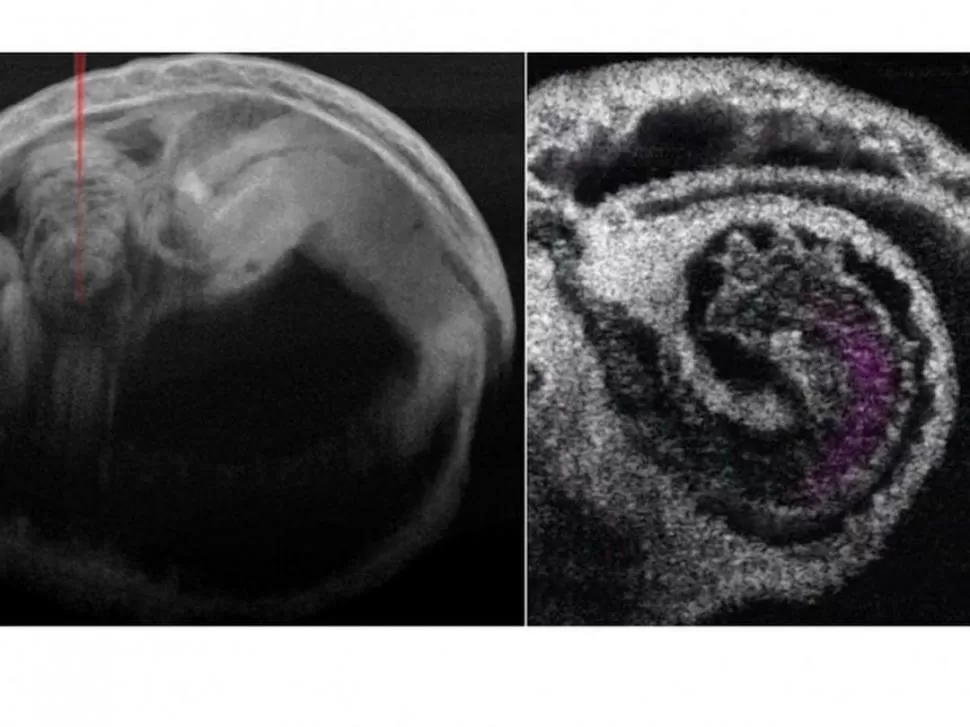

ÚTIL. Con este método se pueden conocer defectos cardíacos congénitos.

Investigadores del Instituto de Tecnología Stevens e Irina Larina del Colegio de Medicina Baylor (Estados Unidos) han utilizado por primera vez la tomografía de coherencia óptica (TCO) en 4D para estudiar el mecanismo de bombeo subyacente al corazón de los mamíferos en desarrollo. Su informe, publicado en la revista Journal of Biomedical Optics, demuestra que la imagen de TCO en 4D del corazón embrionario de un ratón puede proporcionar información sin precedentes sobre cómo funciona el corazón temprano de un mamífero, consigna la agencia DPA.

Profundidad de imagen

Las escalas de imagen únicas y los contrastes dinámicos que ofrece la TCO permiten una profundidad de imagen a nivel milimétrico con una resolución a microescala para capturar todo el corazón del ratón en las etapas medias de la gestación. La TCO también proporciona una visión clara de las finas estructuras cardíacas así como del flujo sanguíneo. La alta velocidad de imagen de la TCO junto con la sincronización post-adquisición permite reconstruir la rápida dinámica del corazón que late.